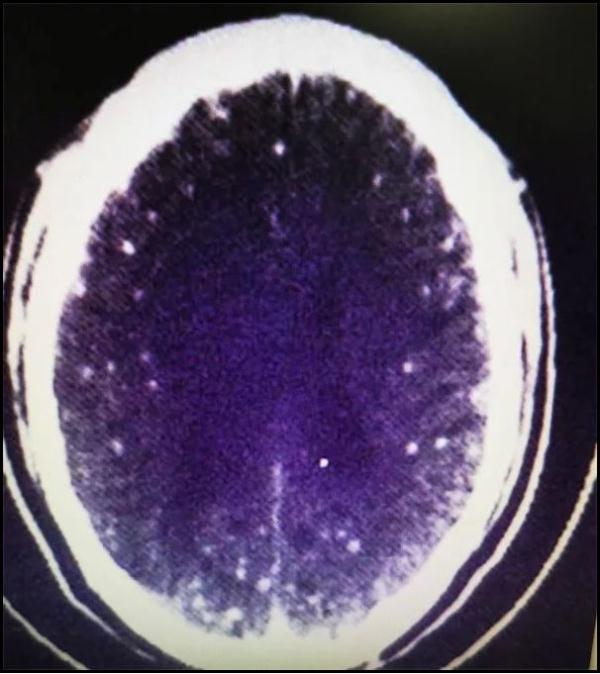

最后发觉,两侧大脑半球存在多发病变情况,再结合血以及脑脊液内囊虫抗体呈现阳性这个结果,从而诊断为脑囊虫病。

颅内CT显示有多个白点病变